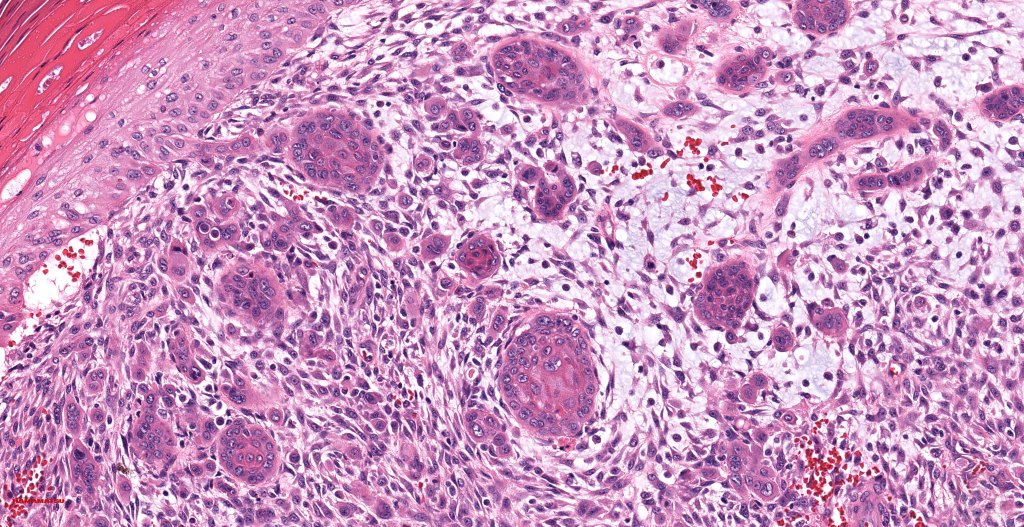

•Biphasic tumor

•Admixture of squamous carcinoma & pleomorphic spindled cell, osteoid, chondroid, MFH-like +/- osteoclast-like giant cells & rarely, smooth muscle, skeletal muscle, myofibroblastic or angiosarcomatous elements